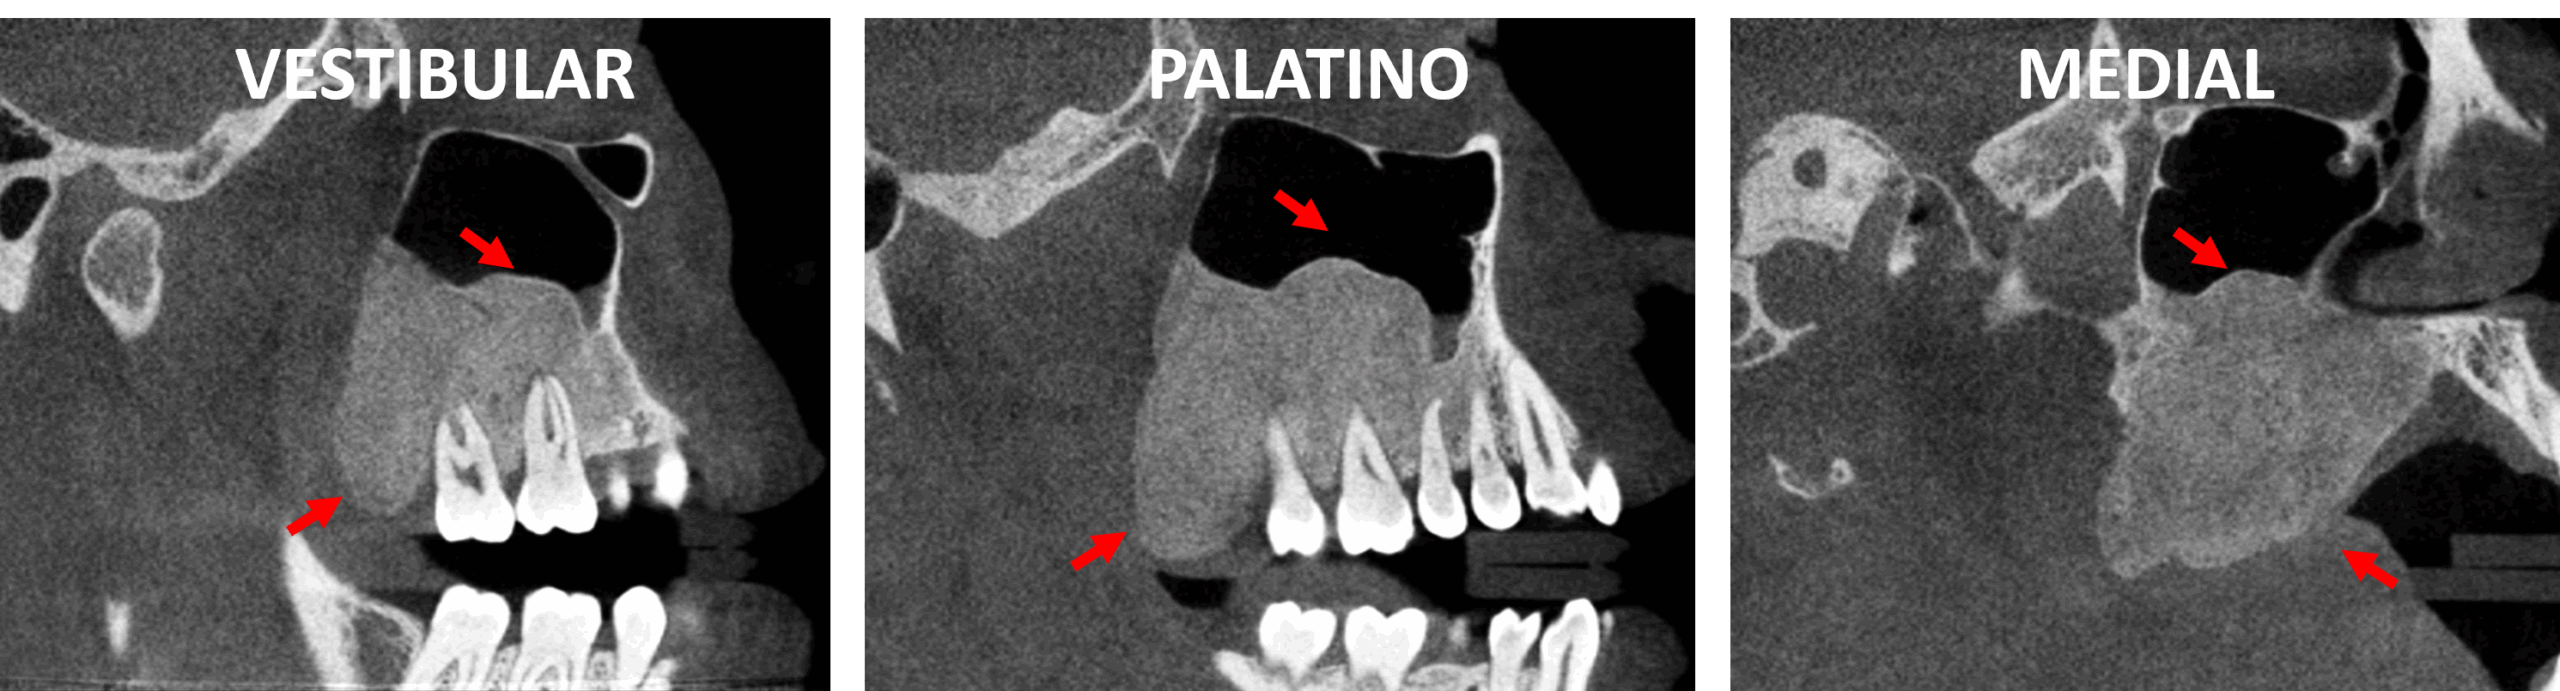

Fig.3

En cortes axiales (Fig,3) se observa la expansión en sentido medio-lateral de la lesion ósea y su extensión hacia el seno maxilar. SE evidencia que la lesion se expande de manera relativamente simétrica, también de forma posterior.